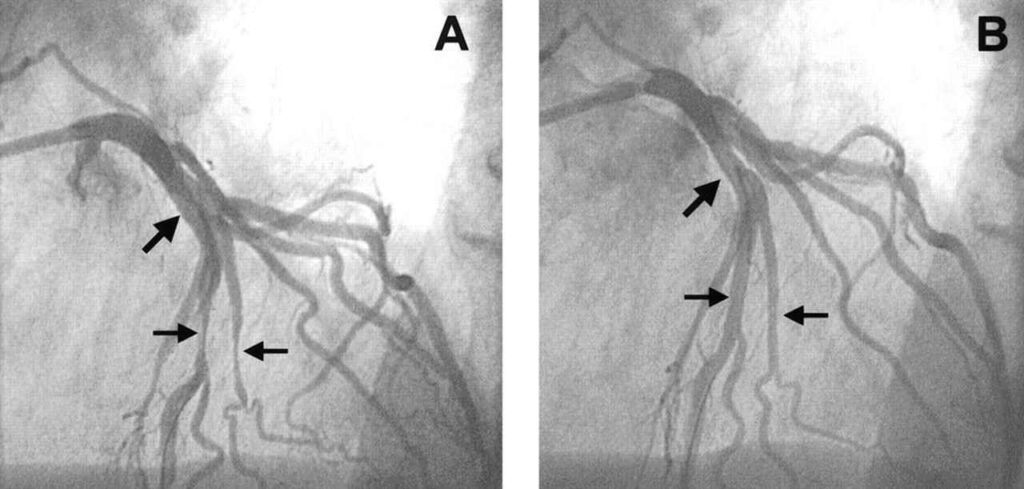

- _آنژیوگرافی تهاجمی (کاتتریزاسیون): دقیق ترین روش که در آن یک لوله باریک (کاتتر) از طریق رگ به قلب فرستاده می شود و ماده حاجب تزریق می شود تا تصاویر زنده و دقیقی از گرفتگی ها ثبت شود.